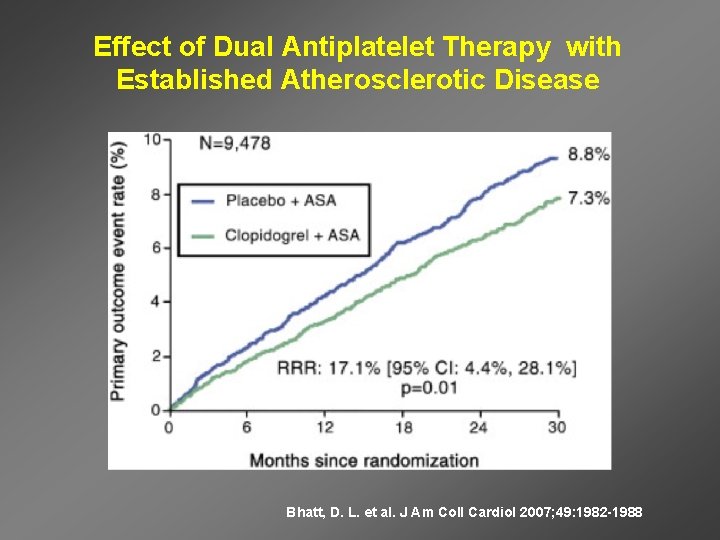

Effect of Dual Antiplatelet Therapy with Established Atherosclerotic Disease Bhatt, D. L. et al. J Am Coll Cardiol 2007; 49: 1982 -1988